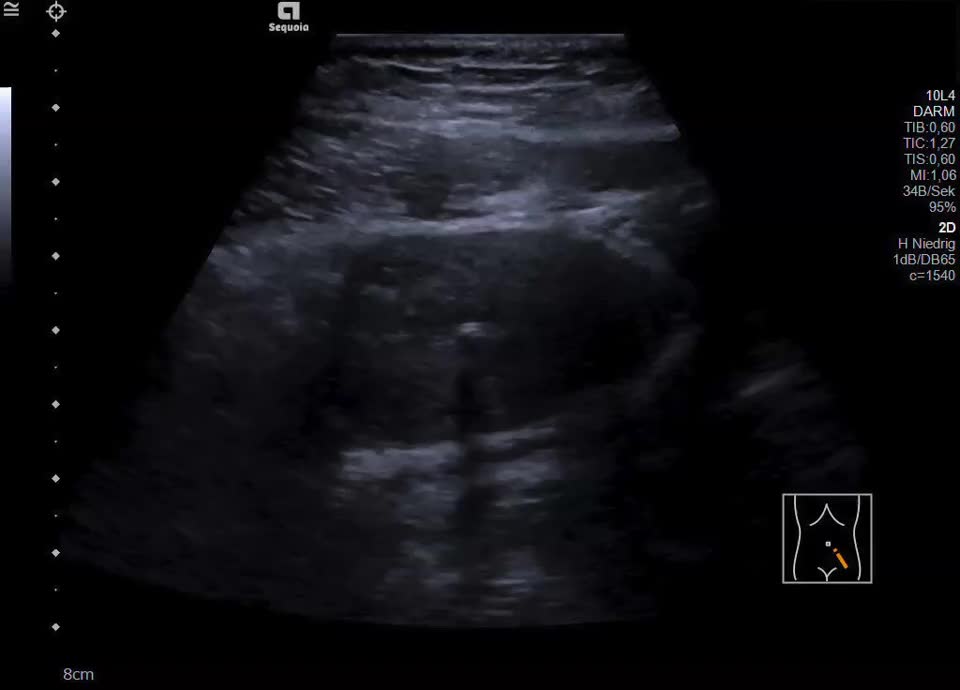

• ovarian cancer

• ovarian cancer (video)